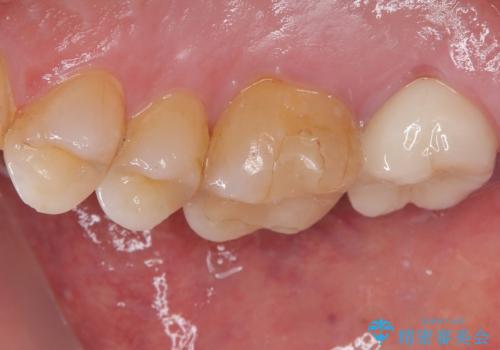

- 食事の時に奥歯が欠けて冷たいものがしみることを主訴として来院された患者様です。

虫歯が詰め物の下で広がっていたこと、もともとの詰め物が大きく健全な歯の量が少なく噛む面に強い力がかかったことが原因で歯が欠けてしまった事が考えられます。

精査の結果、歯肉縁下に破折は認めれられませんでした。

部分的な詰め物では再び割れてしまう可能性が高いため、虫歯を除去し、オールセラミッククラウンにて補綴することとしました。